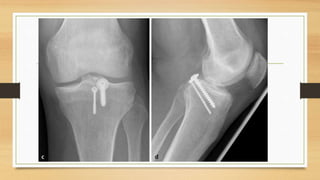

EXAMENES AUXILIARES

Linea de Blumenssat,

cicatriz del cartílago

hialino

EXAMENES AUXILIARES Linea deBlumenssat, cicatriz del cartílago hialino